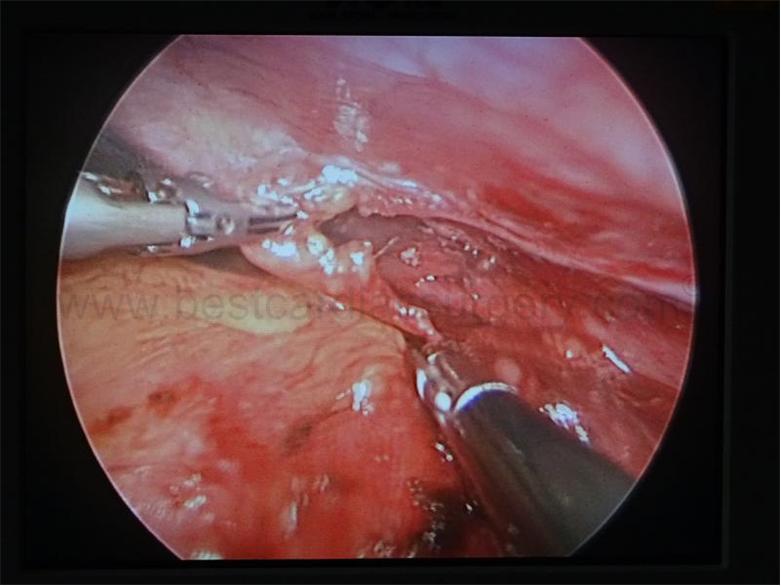

BEST CARDIAC SURGERY – VATS [THORACOSCOPY] & GENERAL THORACIC SURGERY

CARDIO THORACIC AND VASCULAR SURGERY